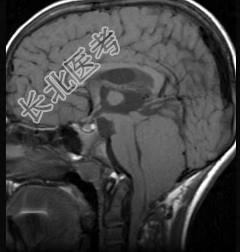

- 多项选择题第四脑室室管膜瘤(如图所示)临床特点包括 ( )

A、颅内高压症状较早

B、多以头痛为首发症状

C、伴有呕吐、头晕及强迫头位

D、肿瘤增大累及小脑蚓部或半球时,可出现平衡障碍、步态不稳和共济失调等

E、当肿瘤压迫脑干或脑神经时,可出现相应的脑神经障碍